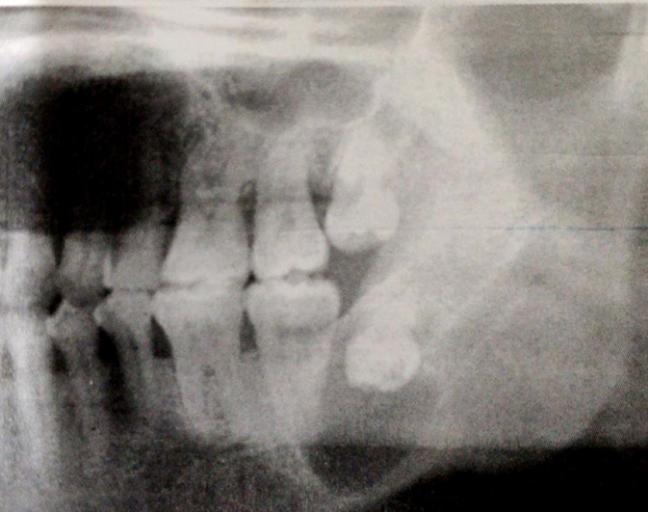

◆ 根尖囊肿:是颌骨内最常见的牙源性囊肿,属于炎症性囊肿,多发生于20-49岁人群。尽管10岁以下儿童龋病发生率不低,但根尖周囊肿并不常见。男性比女性多见,约60%的囊肿发生于上颌,以上颌切牙和单尖牙为好发部位。囊肿大小不等,常与末期龋、残根或变色的死髓牙相伴随。较大的囊肿可导致颌骨膨胀,常引起唇颊侧骨壁吸收变薄,扪诊时有乒乓感。X线显示根尖区有一圆形或卵圆形透射区,边缘整齐,界限清晰,部分病例透射区周围有薄层阻射线。

◆ 牙旁囊肿:发生于阻生下颌第三磨牙的颊侧或远中颊侧,患者常有智齿冠周炎反复发作史,牙齿为活髓。X线显示部分阻生的下颌第三磨牙远中有边界清楚的透射区,有时病变可延伸至根尖部。虽然其镜下表现与根尖周囊肿相似,但根尖周囊肿的患牙为死髓牙,而牙旁囊肿的伴随牙为活髓牙。